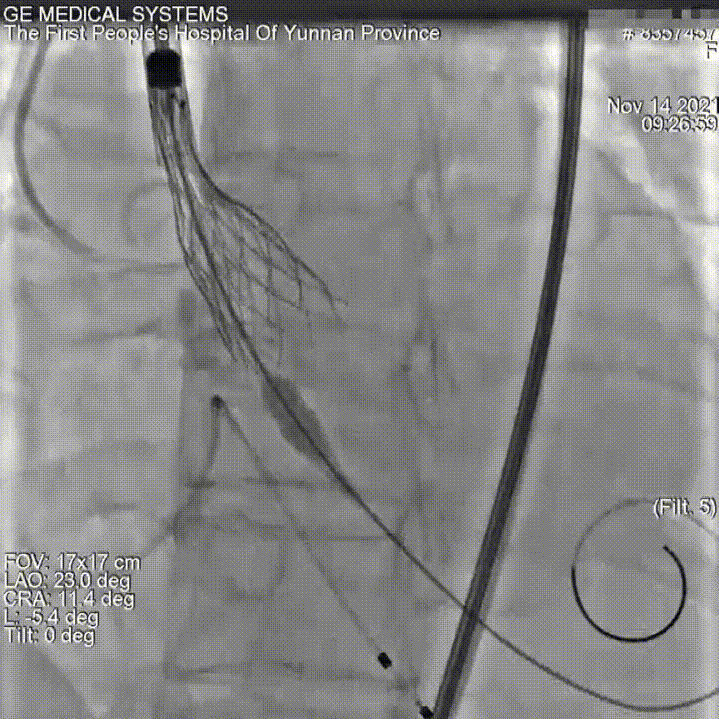

主动脉根部造影

18mm球囊预扩

瓣膜定位

瓣膜释放

术后造影